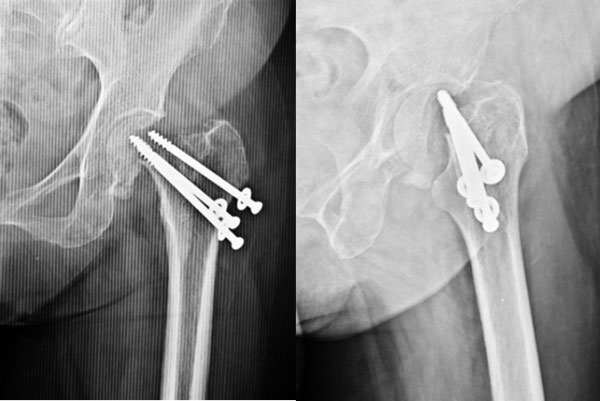

| 2 months after THR |

2 months on the patient is walking well. |